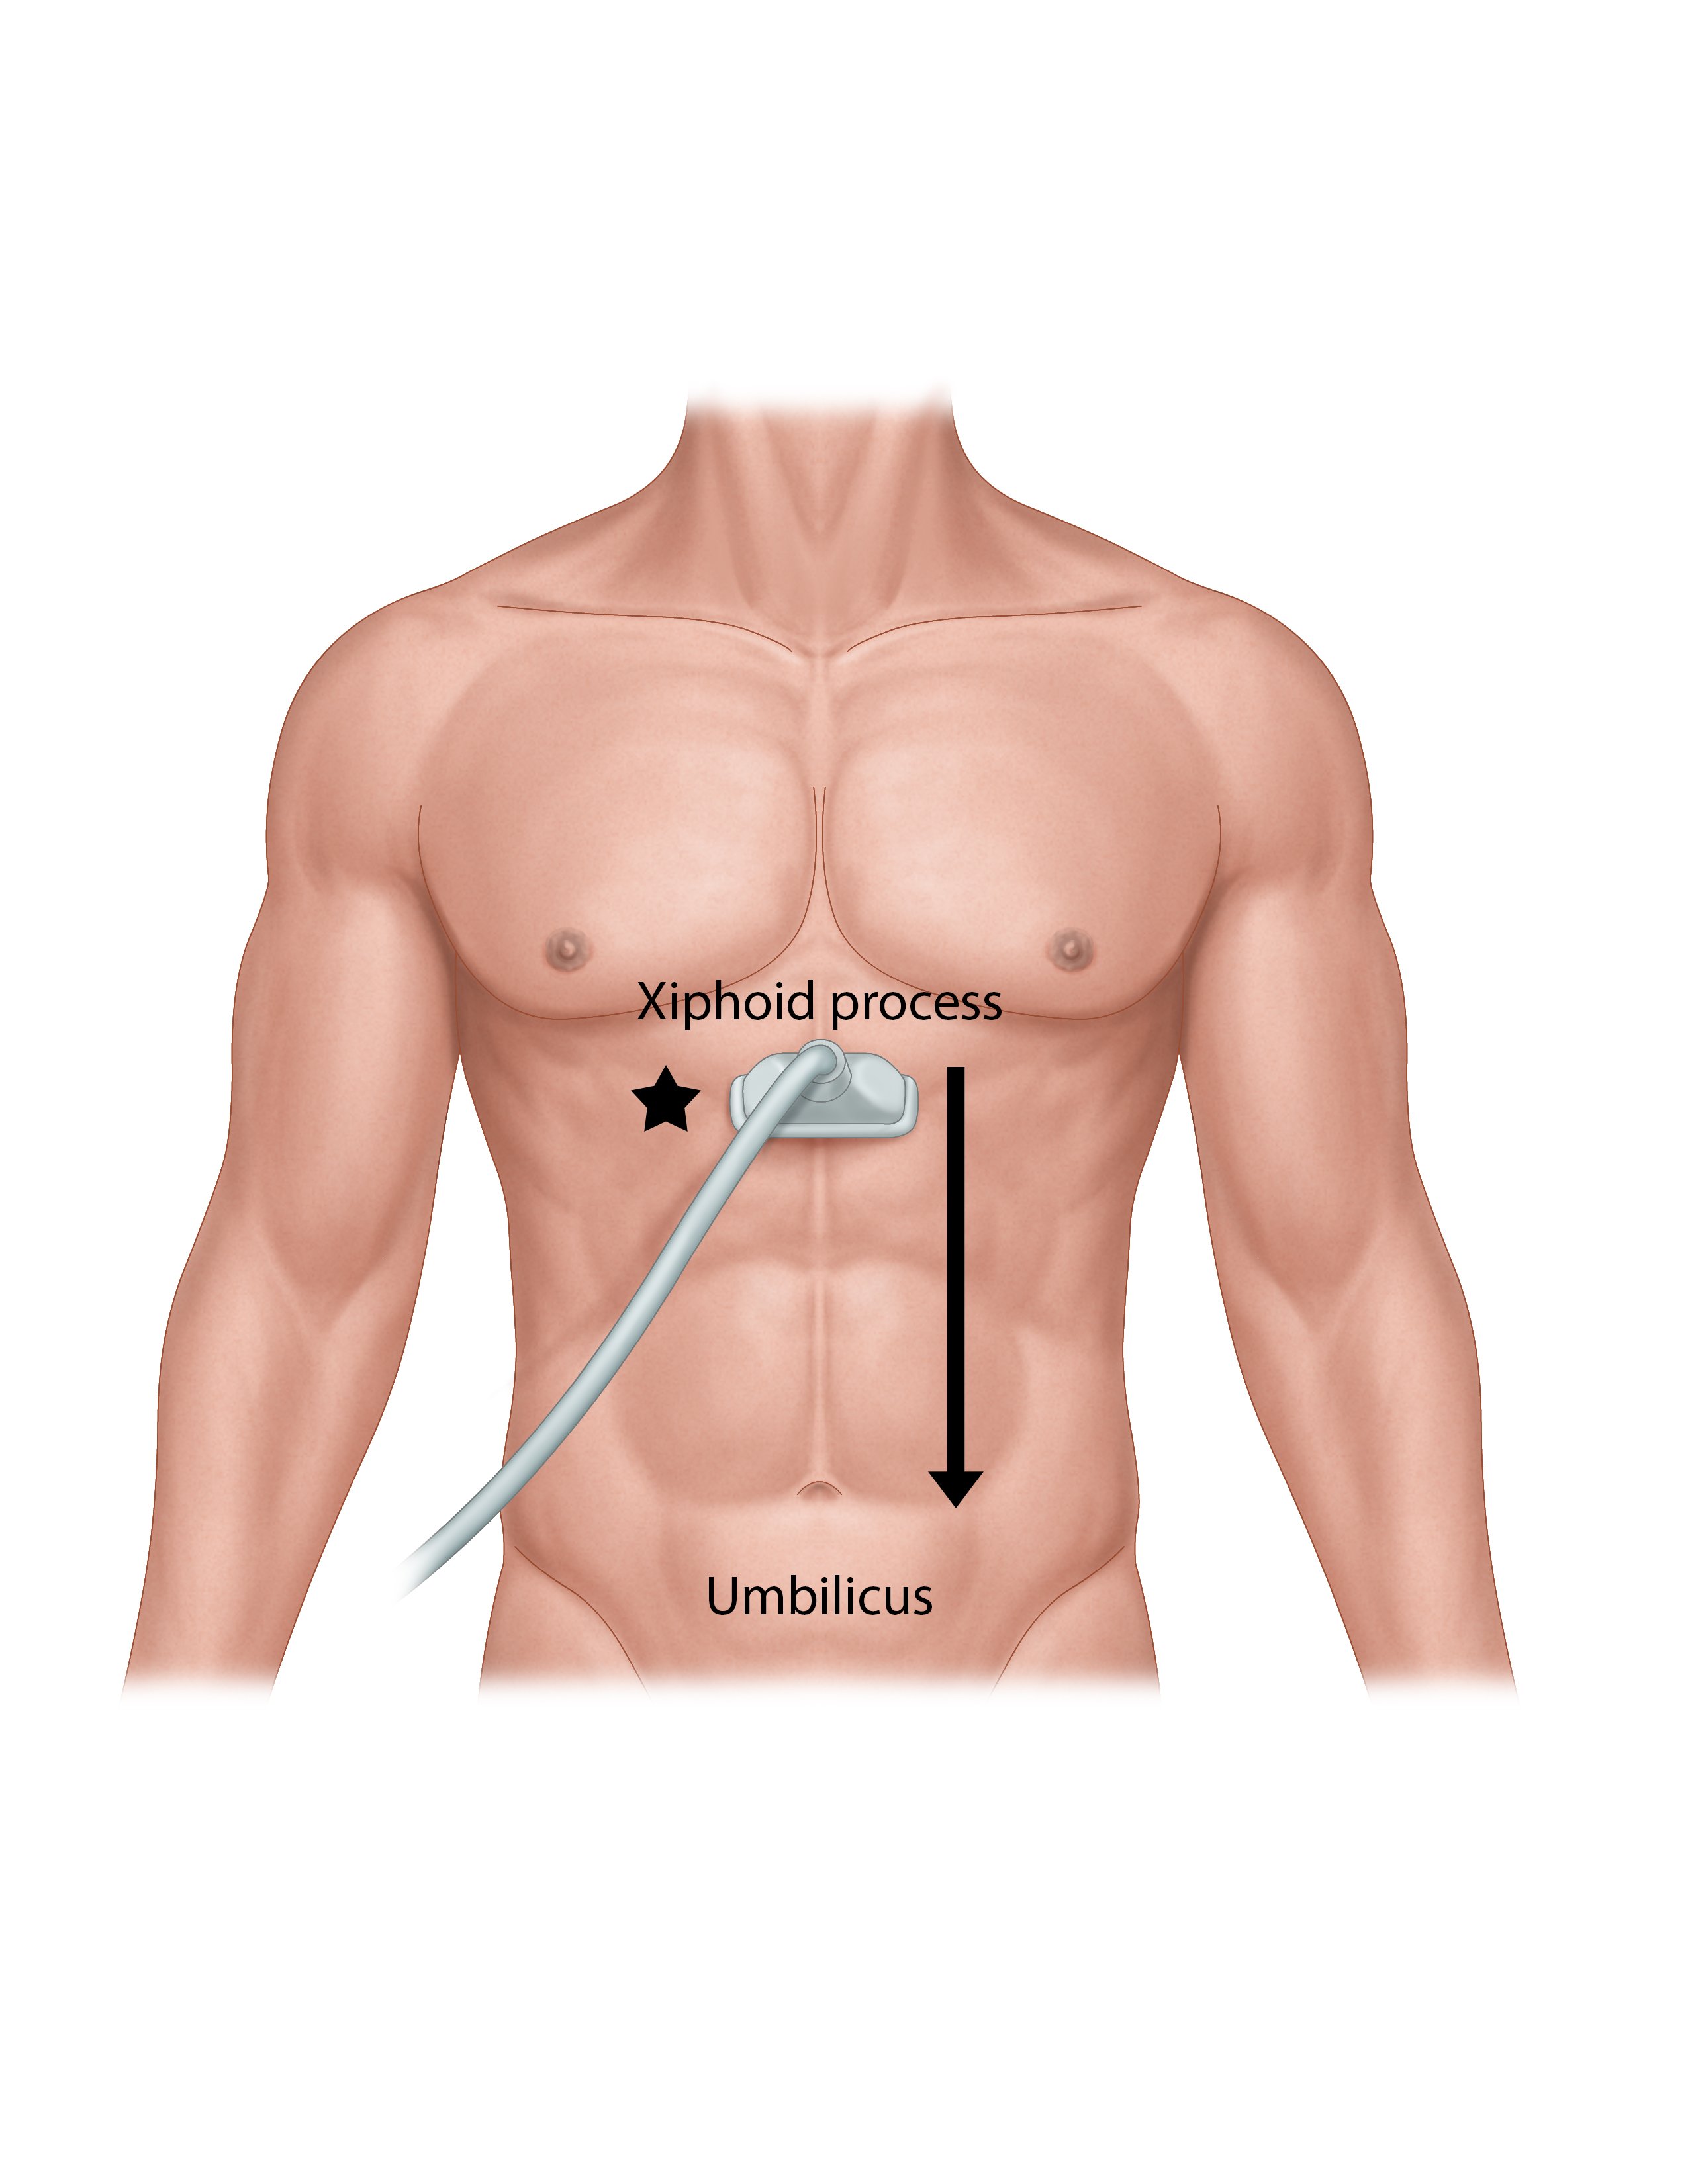

- Abdominal aorta lies slightly to left of midline and bifurcates at the level of the 4th or 5th lumbar vertebral body. (Illustration 1) The surface anatomy landmarks are the xiphoid process and the umbilicus (Illustration 2).

- Illustration 2. Scanning technique. Probe is just inferior to the xiphoid process, indicator towards the patient’s right (star) for a transverse view. Probe is moved inferior to the umbilicus.